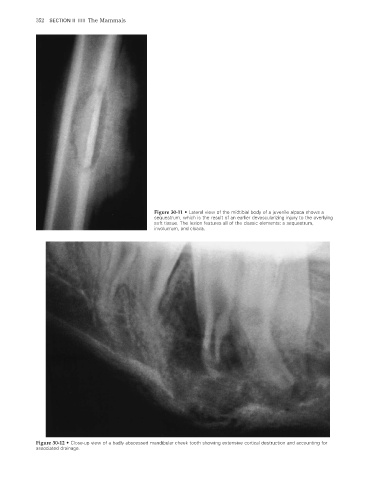

Figure 30-11 • Lateral view of the midtibial body of a juvenile alpaca shows a

sequestrum, which is the result of an earlier devascularizing injury to the overlying

soft tissue. The lesion features all of the classic elements: a sequestrum,

involucrum, and cloaca.

Figure 30-12 • Close-up view of a badly abscessed mandibular cheek tooth showing extensive cortical destruction and accounting for

associated drainage.